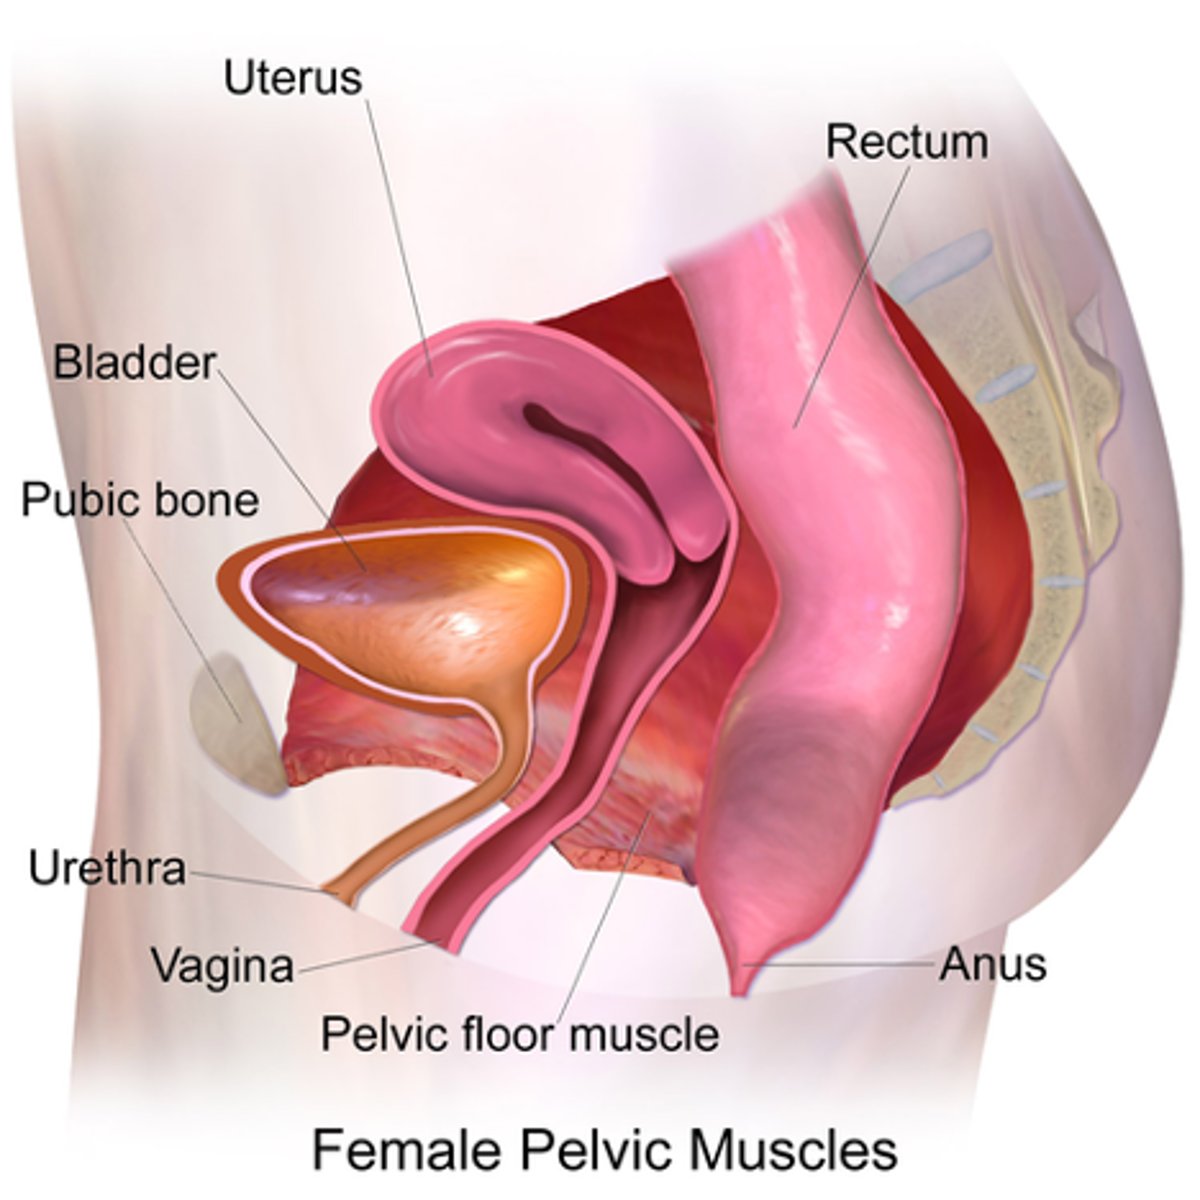

The female pelvis is in the ___ cavity

peritoneal

The pelvis extends from the ____ to the ____

iliac crests; pelvic diaphragm

Obturator internus muscles line the ___ walls of the true pelvis

lateral

Piriformis muscles are in the ___ region of the true pelvis behind the ___

posterior; uterus

What are the 3 levator ani muscles?

pubococcygeus

iliococcygeus

puborectalis